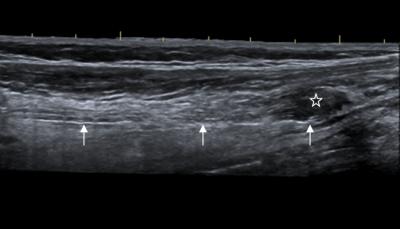

Multiple previous studies of earthquake injuries have focused mainly on crush syndrome, fractures, infections, and rhabdomyolysis. Published data on peripheral nerve injury are very limited and there is no report of the findings on ultrasonographic scans. Dr. Man Lu and co-workers from Sichuan Provincial People's Hospital in China evaluated 34 patients with persistent clinical symptoms and neurologic signs of impaired nerve function, who were selected from 211 patients with clinical signs of impaired peripheral nerves wounded in the Wenchuan earthquake undergoing clinical examination, electrodiagnostic tests, and sonography. Among the 34 patients, the concordance rate of ultrasonography findings with those of surgical results was 98%. Postoperative ul¬trasound follow-up revealed that the majority of patients (86%) had a good recovery after neurolysis, anastomosis or transplantation, showing the better concordance between clinical outcomes and ultrasonographic outcomes. Preoperative and postoperative clinical and ultrasonographic results were concordant, which verified that ultrasonography is useful for preoperative diagnosis and postoperative evaluation of injured peripheral nerves. These findings have been published in the Neural Regeneration Research .

Article: " Follow-up evaluation with ultrasonography of peripheral nerve injuries after an earthquake," by Man Lu1, Yue Wang2, Linxian Yue1, Jack Chiu3, Fanding He1, Xiaojing Wu2, Bin Zang2, Bin Lu2, Xiaoke Yao2, Zirui Jiang4 (1 Department of Ultrasound, Sichuan Provincial People's Hospital, Chengdu, Sichuan Province, China; 2 Department of Orthopedics, Sichuan Provincial People's Hospital, Chengdu, Sichuan Province, China; 3 Department of Radiology, University Hospital, University of Western Ontario, Ontario, Canada; 4 Chengdu Jiaxiang Foreign Languages School, Chengdu, Sichuan Province, China)

Lu M, Wang Y, Yue LX, Chiu J, He FD, Wu XJ, Zang B, Lu B, Yao XK, Jiang ZR. Follow-up evaluation with ultrasonography of peripheral nerve injuries after an earthquake. Neural Regen Res . 2014;9(6):582-588.